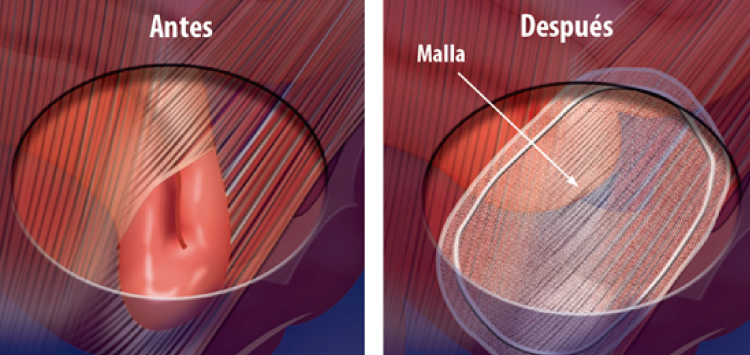

Hernias

Una hernia se presenta en alguna zona de debilidad de la pared abdominal, a través del cual protruye el contenido de la cavidad abdominal pudiendo ser un asa intestinal o tejido graso. Las hernias se manifiestan con dolor que se incrementa con el esfuerzo o movilización y zonas con aumentos de volumen cuyo contenido puede regresar al interior de la cavidad, requiriendo de manejo quirúrgico lo antes posible, ya que puede complicarse con la imposibilidad de retornar el contenido de la hernia hacia el interior sufriendo lesión de los órganos por falta de irrigación y por lo tanto que se requiera de cirugía de Urgencia. Las hernias se pueden presentar a diferentes niveles de la cavidad abdominal o pueden ser secundarias a procedimientos quirúrgicos previos, por lo que realizamos procedimientos quirúrgicos para la atención de:

Realizamos diferentes abordajes y técnicas para la reparación de los defectos herniarios llevando a cabo cirugía abierta o cirugía laparoscópica dependiendo de la valoración de cada caso, además de llevar a cabo la colocación de mallas para evitar la recurrencia. Además contamos con experiencia en el manejo de hernias ventrales grandes, en las que utilizamos diferentes métodos, toxina botulínica y diferentes mallas para lograr el cierre de la pared abdominal.

Hernia Umbilical